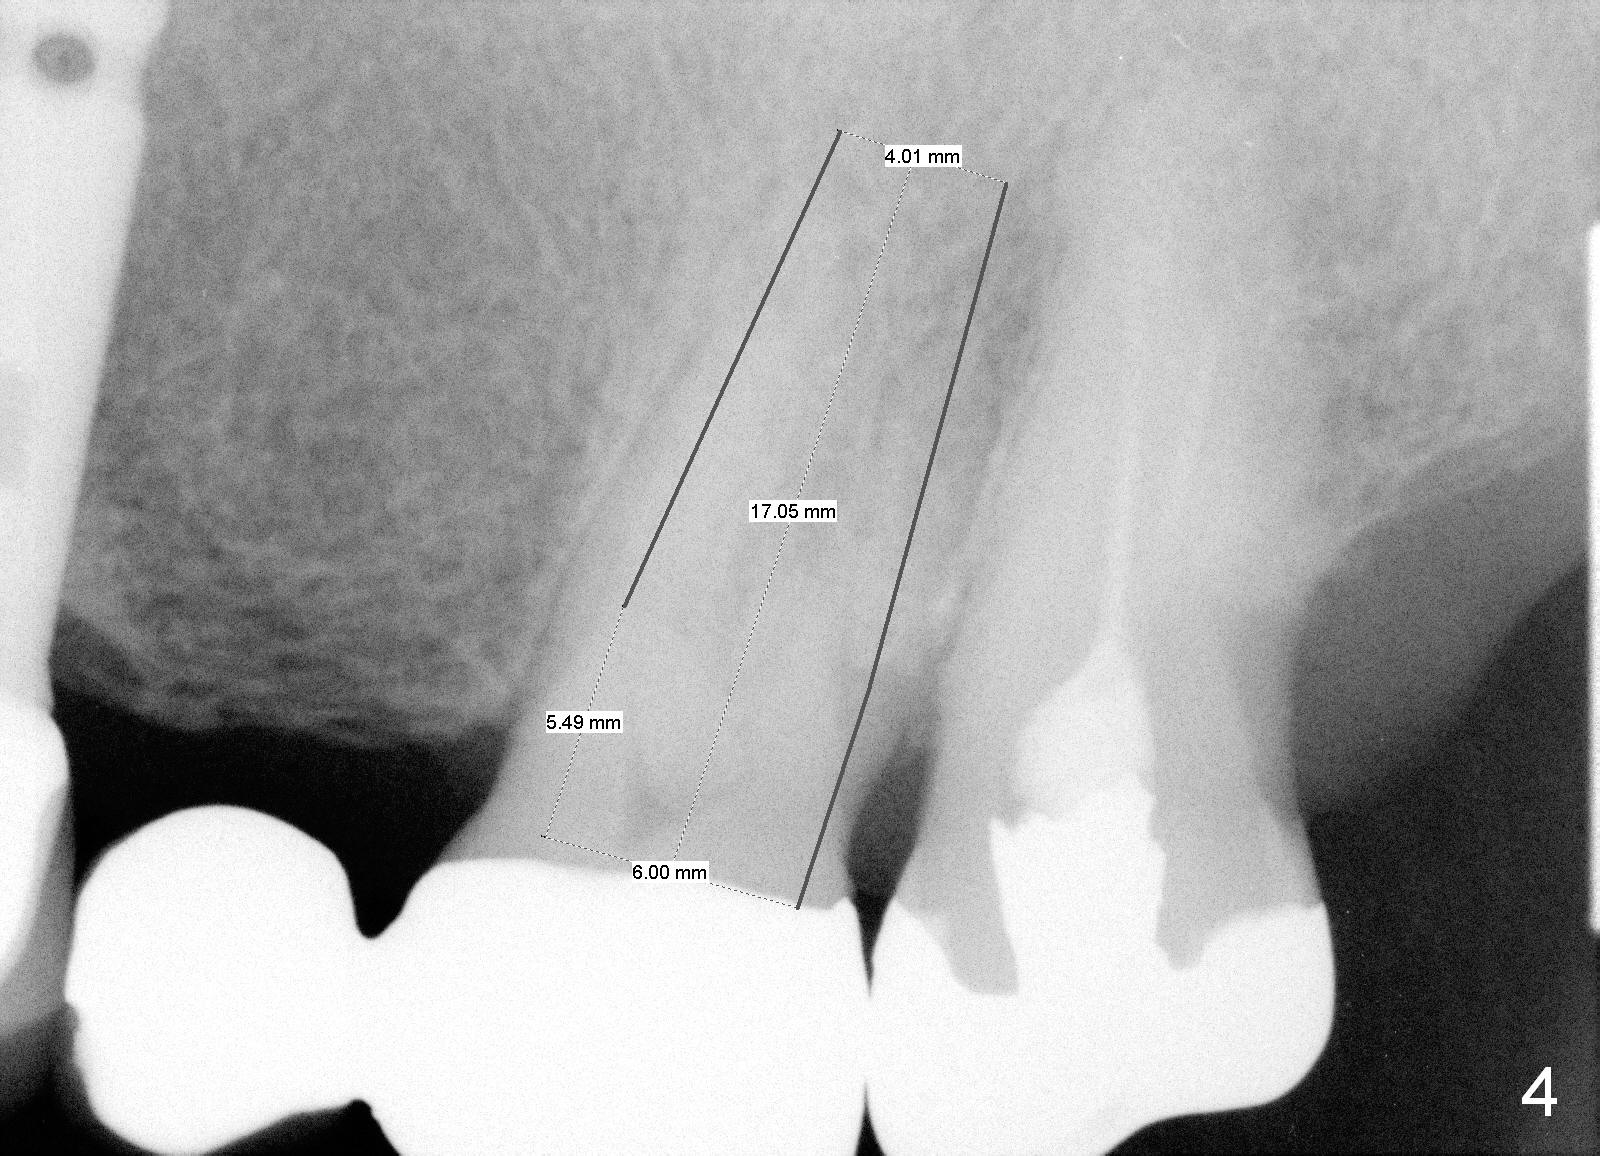

A 71-year-old man has multiple restorations, most of which are high noble crowns (Fig.0). He used to have a cantilever bridge involving the teeth #13 and 14 (Fig.1). It fractures (Fig.2,3). Considering the obliterated canals (Fig.1) and history of "bristle teeth", implants will be the best treatment option. The tooth #14 will be sectioned (Fig.3 upper left inset) for extraction. The osteotomy will be initiated in the septum slightly palatal, as shown by O in Fig.3 so that the immediate implant will be almost obliterating the socket mesiodistally (Fig.2 upper right inset white circle). The implant is also contacting the palatal wall of the socket and the buccal septal strut (pink outline) for primary stability. It appears that a 6x17 mm tissue-level implant is able to occupy the mesiodistal space (Fig.4) and that a 7 mm may be a better option. There is enough bone height for a 20 mm long implant.